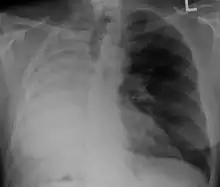

![]() Appearance of the cut surface of a pneumonectomy specimen containing lung cancer, here a squamous cell carcinoma (the whitish tumor near the bronchi). | |

Anatomical changes

After a pneumonectomy is performed, changes in the thoracic cavity occur to compensate for the altered anatomy. The remaining lung hyperinflates as well as shifting over along with the heart towards the now empty space. This space is full of air initially after surgery, but then it is absorbed, and fluid eventually takes its place.[9] The fluid which fills the residual space in the chest cavity slowly gelatinizes into a proteinaceous material, and the chest scaffold collapses slightly.